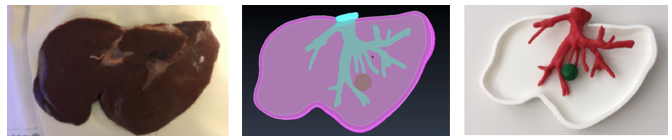

Figure 32 shows the result of the printed models.

Draft Samper 627449012 5415 Fig32.png

Figure 32. Printed models

As it is observed in Figure 33, the printed liver correctly corresponds in shape to the animal's liver, indicating that the steps in the post-processing of the model resulted in optimised anatomical representations, increasing the performance of the HoloLens™ application while minimising loss of model precision.

Draft Samper 627449012 4479 Fig33.png

Figure 33. Comparison: animal's liver, segmented and printed model